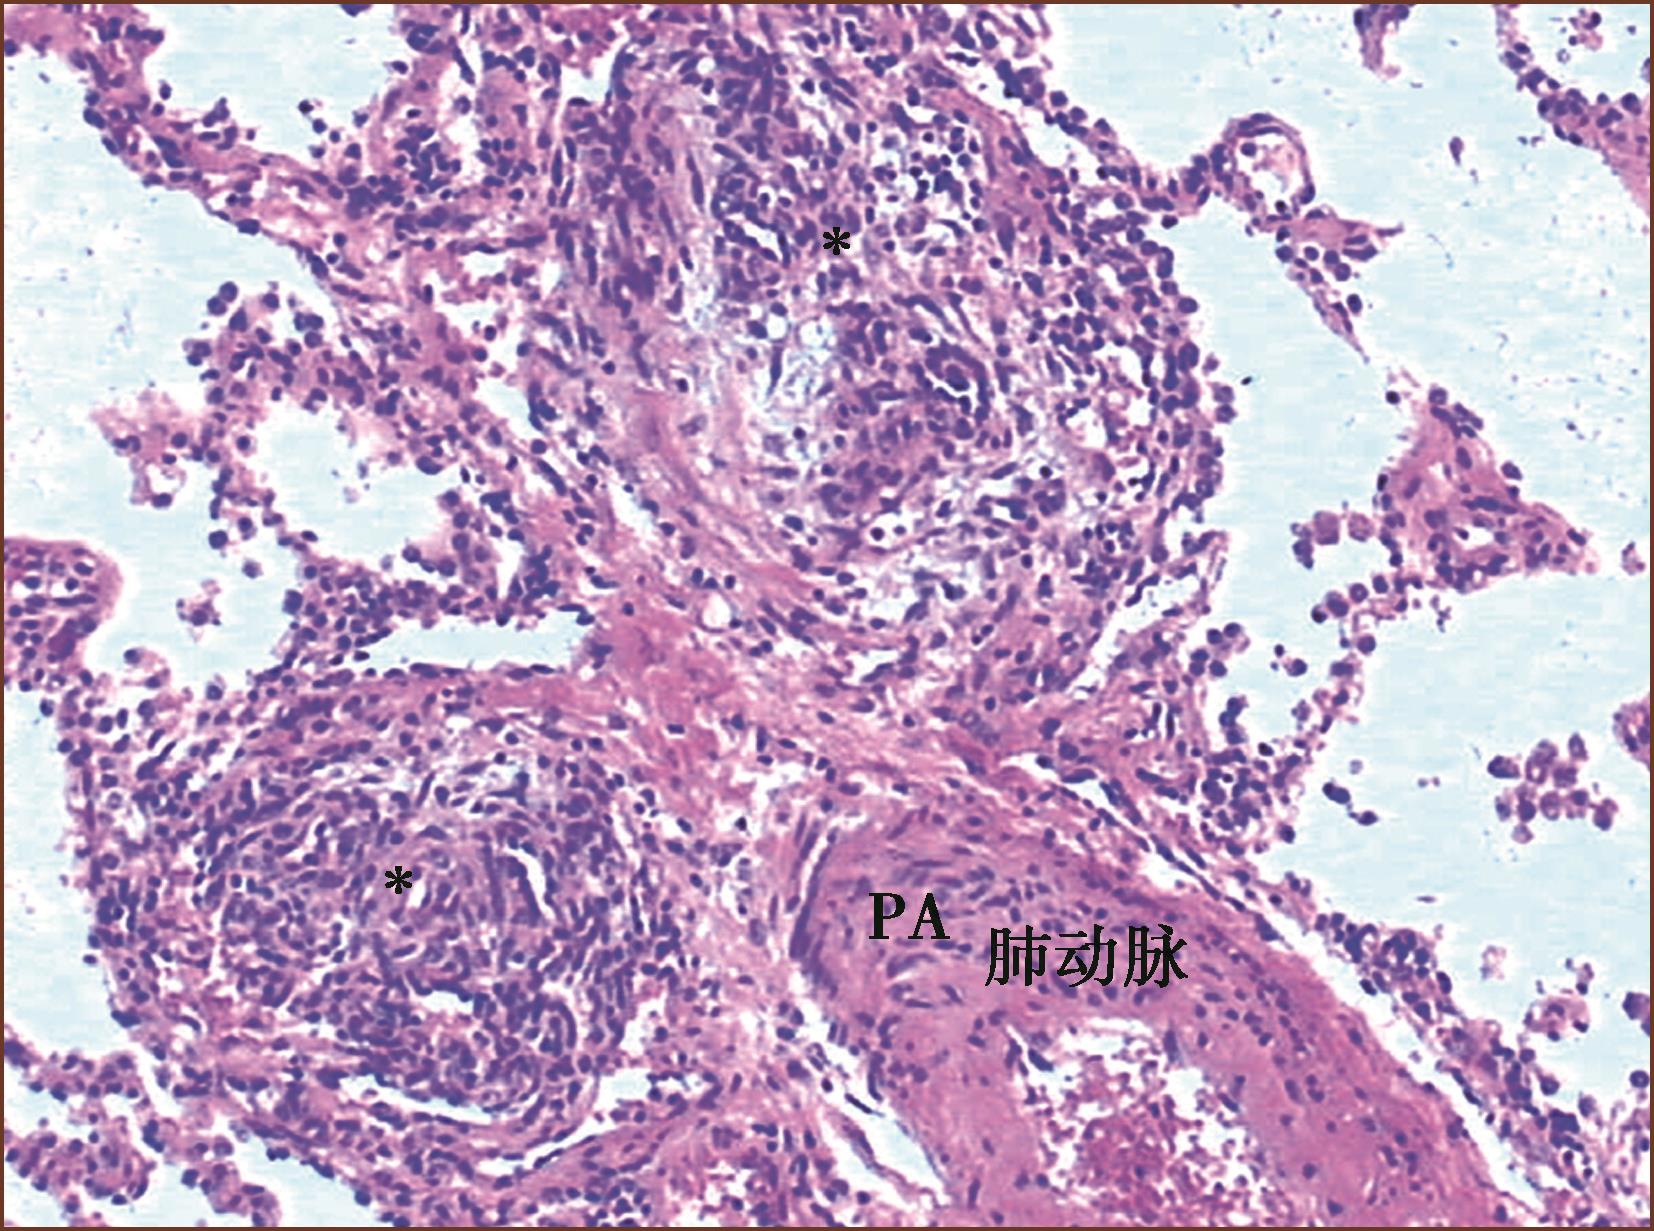

丛状病变组织学显示由无规律生长的内皮细胞团(丛)状增生(有作者认为是肿瘤性内皮细胞增生)(图3-1-12,图3-1-13)。丛状病变组成成分有新生内皮细胞团(丛),混杂有肌纤维母细胞、平滑肌细胞和结缔组织基质,形成灶性薄壁的多个毛细血管裂隙。丛状病变的内皮细胞可被血管内皮生长因子(VEGF)和它的受体标记;用α-SM-Actin可以标记丛状病变内的肌纤维母细胞。有的作者形容丛状病变为血管球样生长。有时,丛状病变的管腔宽大,病变类似动静脉畸形。如果管腔内含有纤维素,要与机化血栓进行鉴别。在临床PAH中,丛状病变在肺活检组织中不易见到。在重症PAH一张组织切片上能见到一两处丛状病变,因此至少应该检查10个肺组织块,才能够除外丛状病变。有研究报道,特发性肺动脉高压的丛状病变为单克隆来源;反之在继发性肺动脉高压的丛状病变是多克隆来源。

图3-1-12 IPAH患者的肺小动脉的丛状病变(HE,中倍放大)

图3-1-13 先天性心脏病患者的肺小动脉的丛状病变(HE,中倍放大)

丛状病变可见在肺小动脉腔内(见图3-1-5)、好发于血管分叉处;也可侵入血管向肺小动脉外形成管壁外丛状病变(见图3-1-13);在丛状病变内还可见纤维素新血栓和血小板积累(图3-1-14)。丛状病变在PAH的发生率变异很大,有报告累及肺动脉分支的20%~60%。

图3-1-14 来自IPAH患者的肺小动脉丛状病变,多个厚薄不一、形状多样的小血管球状及丛状增生,即丛状病变,周围有组织坏死及大量淋巴细胞浸润,为坏死性动脉炎(HE,中倍放大),F:丛状病变

图3-1-16 来自IPAH,图右上方肺小动脉腔呈筛孔状,腔内可见注射的深色钡剂(∗),图中下部的丛状病变裂隙内血管无钡剂,其他薄壁血管为扩张的肺小动脉(HE,高倍放大)